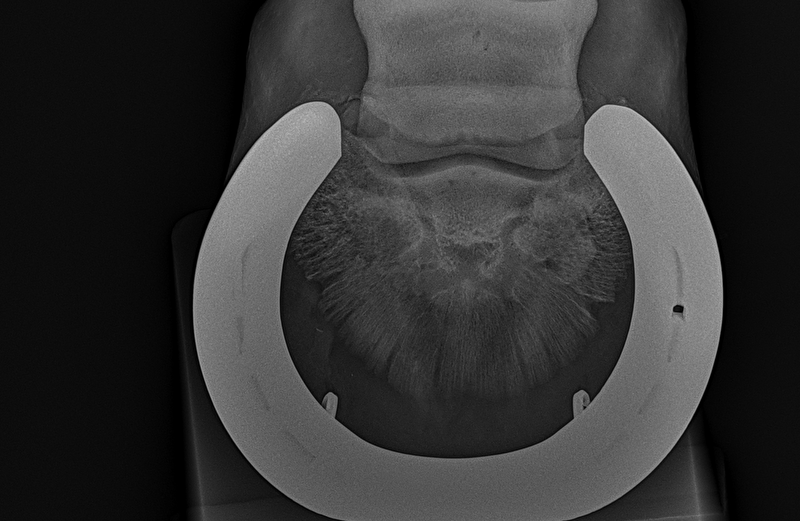

Insups schreef:Ik heb in 2022 een paard gekocht en volledig laten keuren. Die was door dierenarts 1 volledig in orde verklaard. Nu worden er nieuwe foto's gemaakt en blijkt hier toch een opmerking te zijn... Puur uit interesse ben ik benieuwd naar wat jullie zien